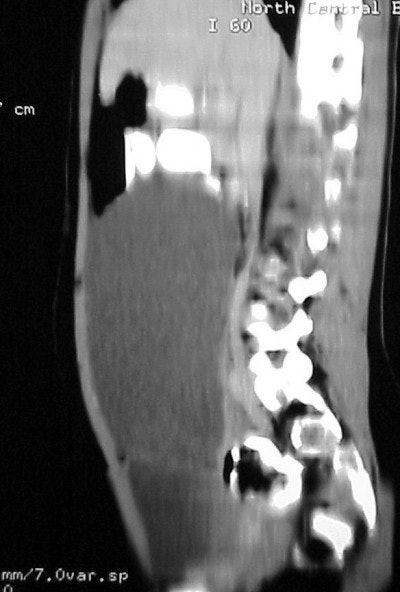

In figure TC 3 we can see a large soft-tissue mass measuring approximately 9 cm wide by 6 cm in AP diameter, and 14 cm in height. It contains both fluid and semi-solid components of soft tissue as well as assorted calcifications. The mass appears to terminate (Figure TC 4) just above the level of the uterus (arrow).

The images (Figures TC 5 and TC 6) show, respectively, a sagittal and coronal MPR of the axial images, demonstrating the size and volume of the structure.